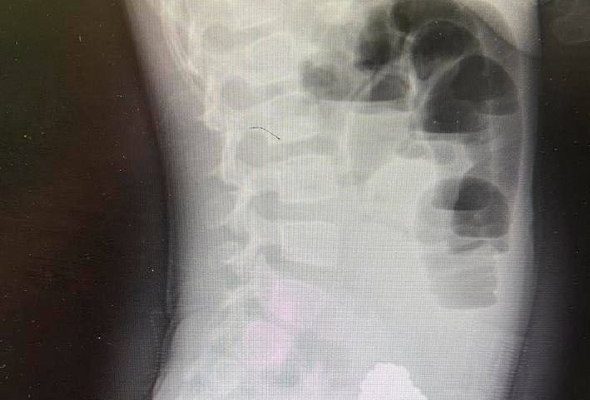

Девочку экстренно доставили в Клиническую больницу скорой помощи №7. При обследовании врачи диагностировали кишечную непроходимость, вызванную инородным телом. Рентгеновское исследование показало скопление слипшихся магнитных шариков, которые сдавливали стенки кишечника.